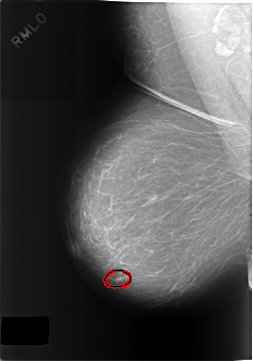

FILE: C_0317_1.RIGHT_MLO.OVERLAY

TOTAL_ABNORMALITIES 1

ABNORMALITY 1

LESION_TYPE MASS SHAPE OVAL MARGINS MICROLOBULATED

ASSESSMENT 3

SUBTLETY 5

PATHOLOGY BENIGN

TOTAL_OUTLINES 1

BOUNDARY